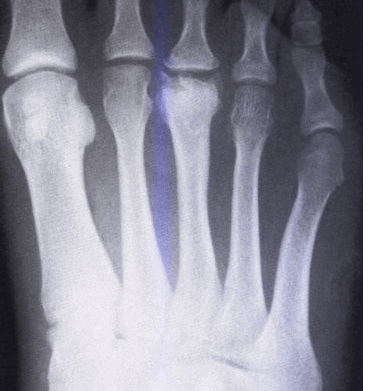

- Болезнь КеллераII. На снимках выявляются патологические изменения в головке пораженной плюсневой кости. В зависимости от срока заболевания может обнаруживаться остеопороз, уплотнение и деформация головки плюсневой кости, ее патологический перелом и дефрагментация.

КТ стопы. Болезнь Келера-2 (остеохондропатия головки 3-й плюсневой кости: снижение высоты головки вследствие остеонекроза, с наличием свободного костно-хрящевого фрагмента).

Рентгенологические признаки болезни Келлера. Ранние стадии заболевания характеризуются остеолизом и центральным коллапсом головки

Рентгенологические признаки болезни Келлера. Поздние стадии заболевания: центральный коллапс и остеолиз головки.

Рентгенограмма на которой отмечается формирование крупного остеофита (стрелка) в области третьего плюснефалангового сустава.